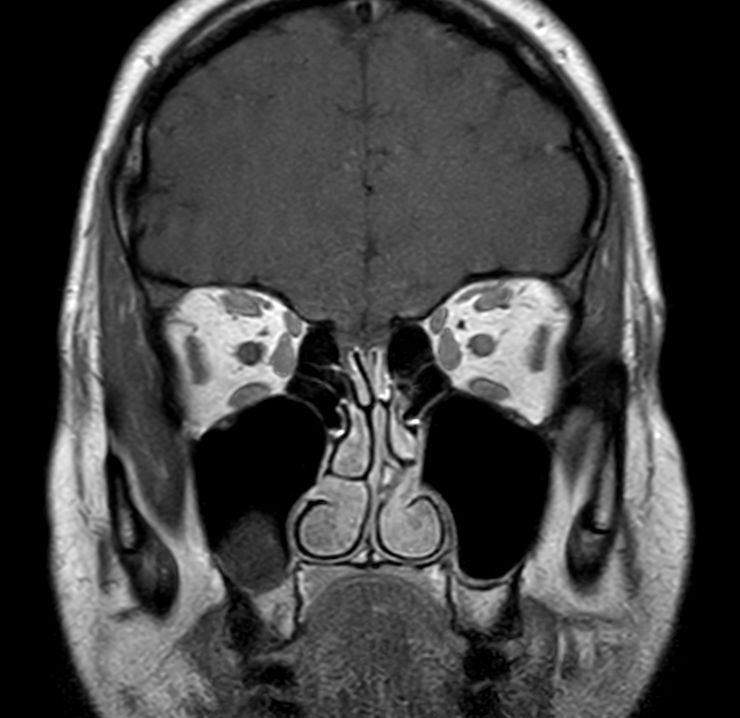

Coronal T1w TSE mDIXON (In Phase)

Pre-Gado

Coronal T1w TSE mDIXON (Water only)

Post-Gado